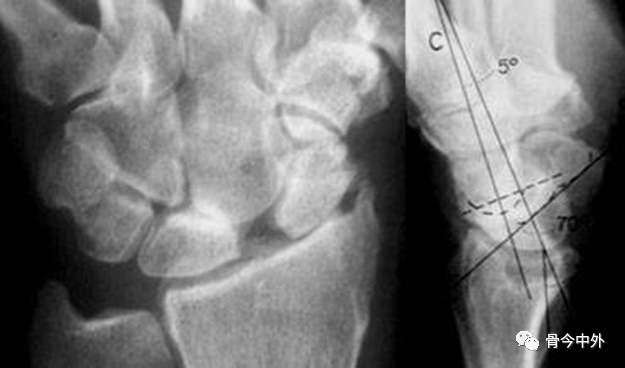

图12 a.桡骨纵轴线;b.桡骨纵轴线垂线;c.桡骨远端关节面切线;d.舟骨轴线;e.月骨轴线;f.头状骨轴线;A桡骨前倾角。

A.正常为0~20˚。若此角度改变,提示桡骨远端骨折。

- ①桡月角(-15°~15°)

- ②桡舟角(30°~60°)

- ③舟月角(30°~60°)

- ④头月角(-15°~15°)

- 在腕骨脱位、半脱位及腕关节失稳时,腕角表现异常。